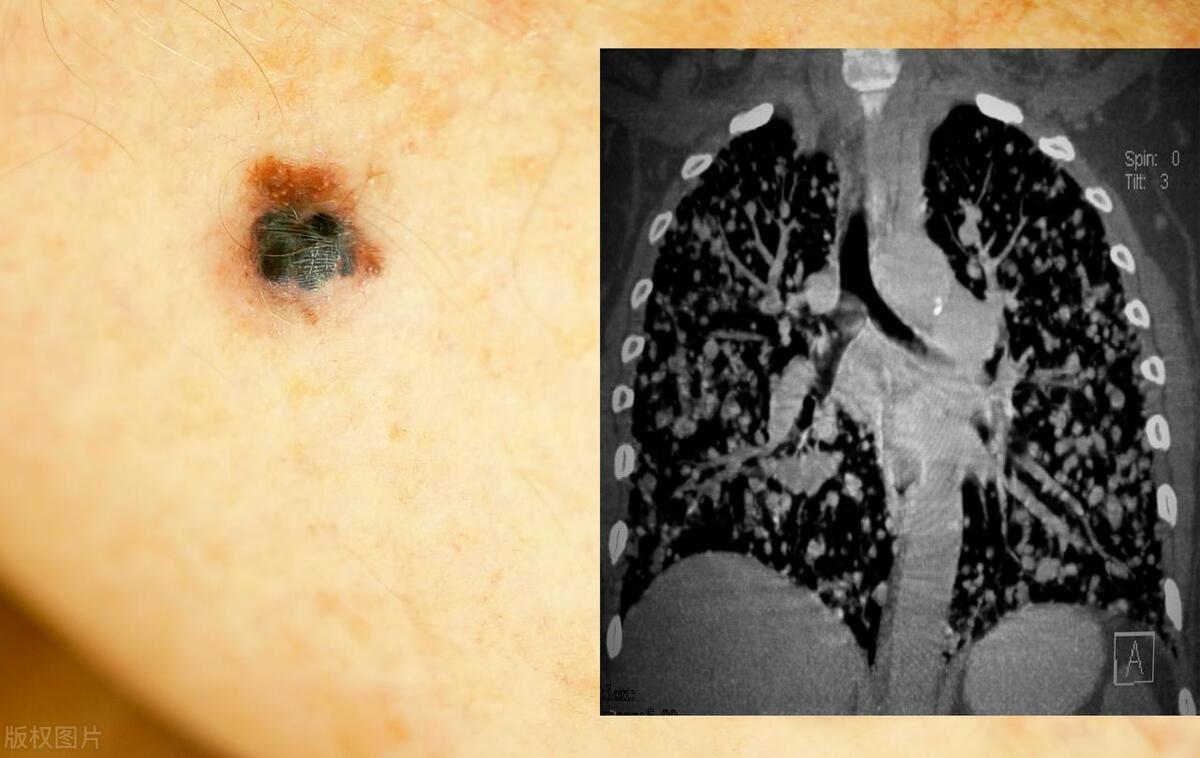

惡性黑色素痣初期的識別與應對,惡性黑色素痣初期識別與防治攻略

摘要:惡性黑色素痣初期識別與應對至關重要。初期癥狀包括皮膚出現黑色或棕色的痣,形狀不規(guī)則,邊緣不整齊,顏色不均等。若出現這些癥狀,應及時就醫(yī)進行專業(yè)檢查。治療方法包括手術切除、放療和藥物治療等。早期識別和治療有助于提...